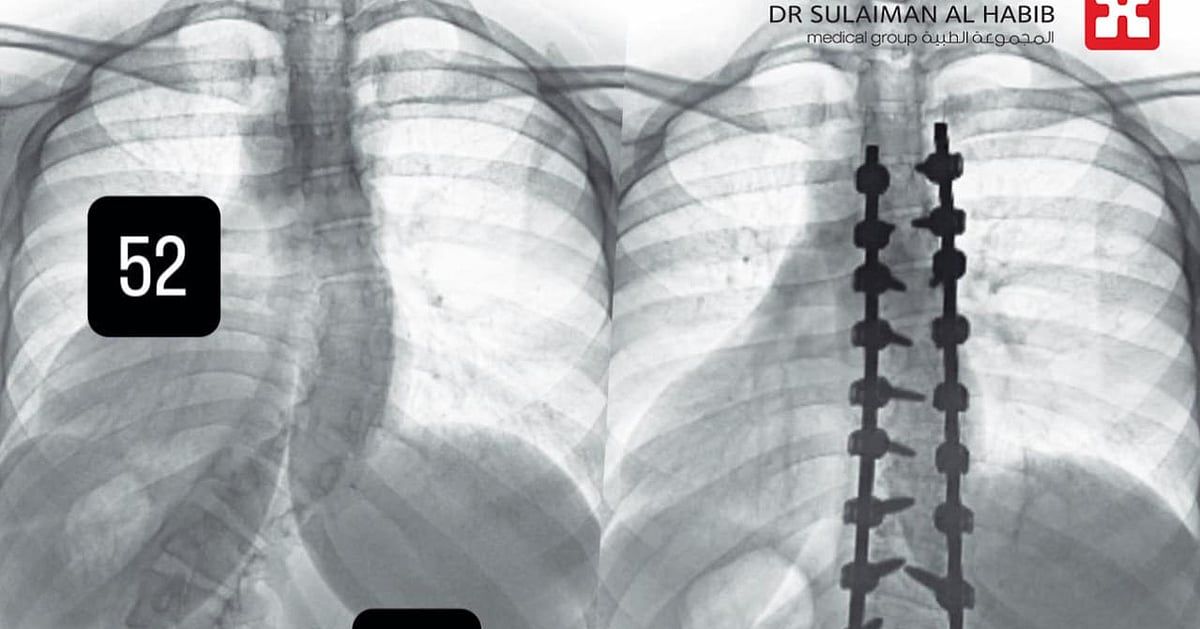

وأجرى لها الفريق الطبي، حزمة من التحاليل والفحوصات الطبية الدقيقة، التي بينت إصابتها بحالة انحراف بجنف درجته "52" بالفقرات الصدرية وآخر بدرجة "72" في الفقرات القطنية، ودرس الفريق الطبي الحالة على ضوء نتائج الفحوصات والتحاليل، وخلص إلى ضرورة التدخل الجراحي لعلاج العيوب، والحد من المضاعفات، وأخضعت الفتاة لعملية جراحية، تم فيها تقويم العمود الفقري بعدد "26" من البراغي والقضبان المعدنية من التايتانيوم والكوبالت كروم والطعوم العظمية الصناعية وتثبيت ودمج الفقرات، وشارك في العملية التي استمرت لـ"6" ساعات، فريق تخدير وتمريض متمرس، واستخدمت فيها مجموعة من أحدث الأجهزة الطبية، التي ساهمت مع الكوادر الطبية عالية الكفاءة والتأهيل بالمستشفى في إنجاحها، ونقلت المريضة إلى جناح التنويم بعد العملية، حيث بدأت في التحسن بشكل متسارع بعد خروجها من غرفة العمليات، إذ استطاعت الوقوف والمشي خلال "24" ساعة، مع فريق العلاج الطبيعي المتمرس، كما أن طولها مع النجاح الكبير للتعديل زاد نحو "4" سم، وخرجت من المستشفى وهي بصحة جيدة، وتوقع أن تستعيد كامل القدرة على الحركة الطبيعية لاحقاً.